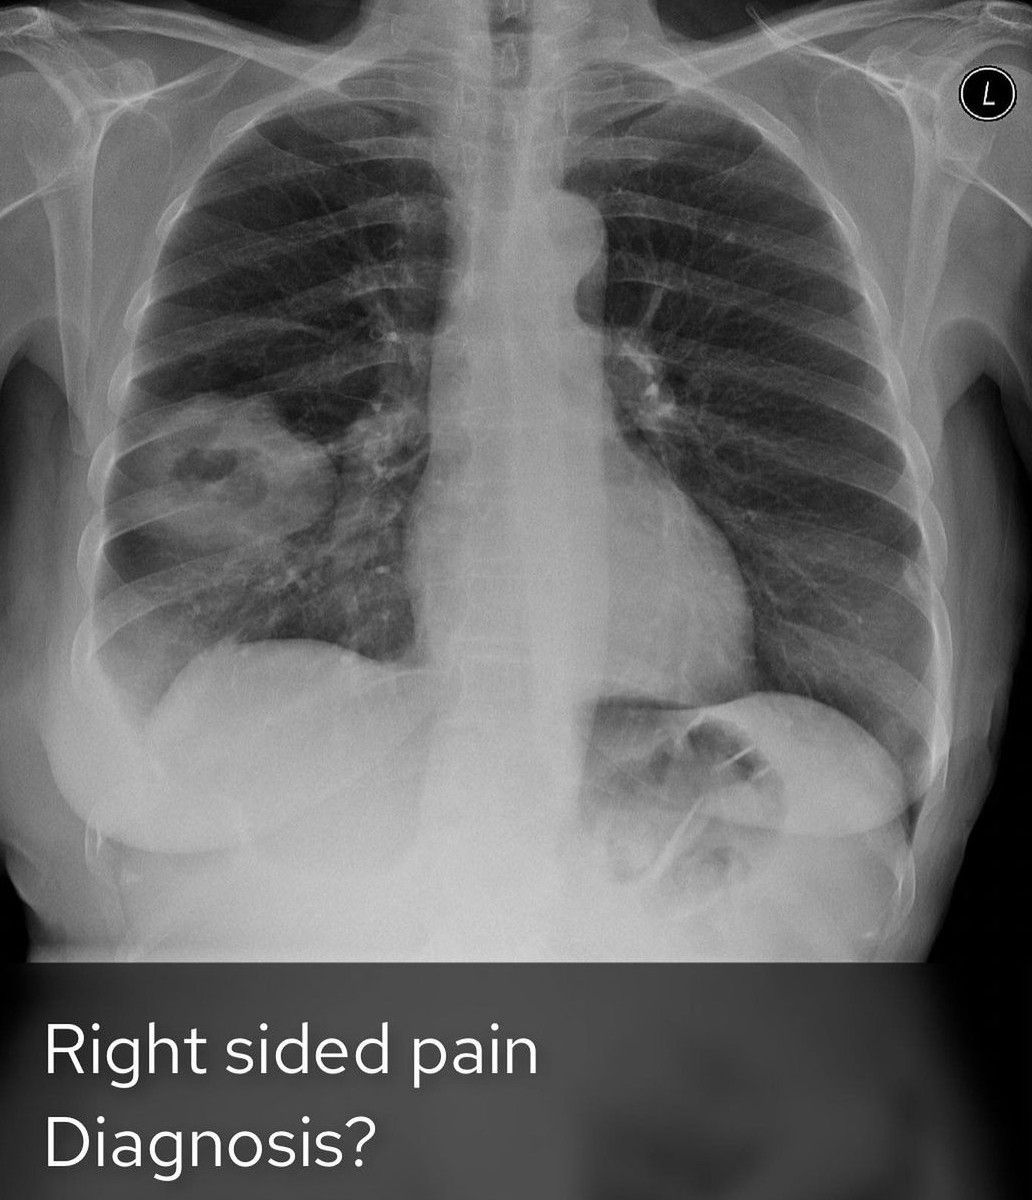

Diagnose It

Diagnose the case with the given radiological presentation.

Diagnosis

Radiology